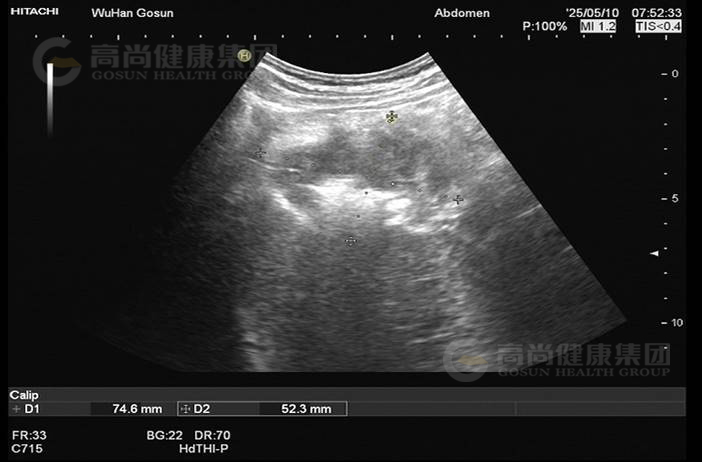

· 超声图像

图2-肝肾间隙包块

图3-肝肾间隙包块

图4-肝肾间隙包块

超声表现及意见:

肝肾间隙可见不均质包块,大小约7.5×6.5×5.2cm,界欠清,轮廓欠规整,壁厚,部分切面周边见高回声晕,内回声不均匀,呈假肾征,包块内部及周边血流信号不明显。

超声提示:

肝肾间隙不均质包块,考虑结肠或腹膜来源,建议进一步检查。